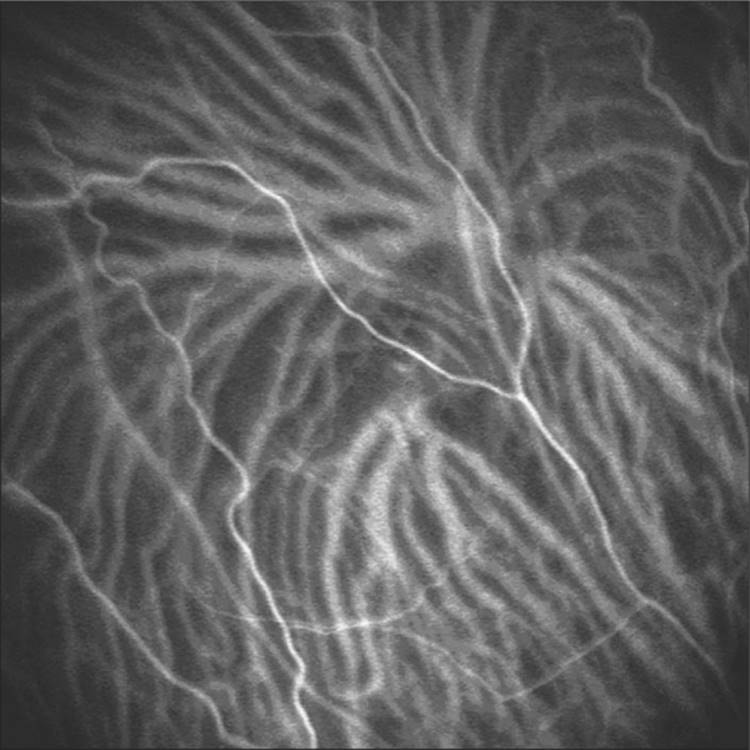

Some branches of these short posterior ciliary arteries are selectively directed to the macular region vessels, i.e., the very short posterior ciliary arteries.[38] Histological examination showed that they have a spiral shaped configuration, consistent with the vascular pattern of the arterial phase of ICG angiography. This pattern differs from short posterior ciliary arteries not directed to the macular area, in that it expands in a typical chevron configuration (Fig. 126.3).[39]

Click to view full size figure

FIGURE 126.3 After scleral penetration the short posterior ciliary arteries expand toward the periphery with a chevron configuration. Indocyanine green angiograms showing choroidal arterial filling with a chevron pattern.